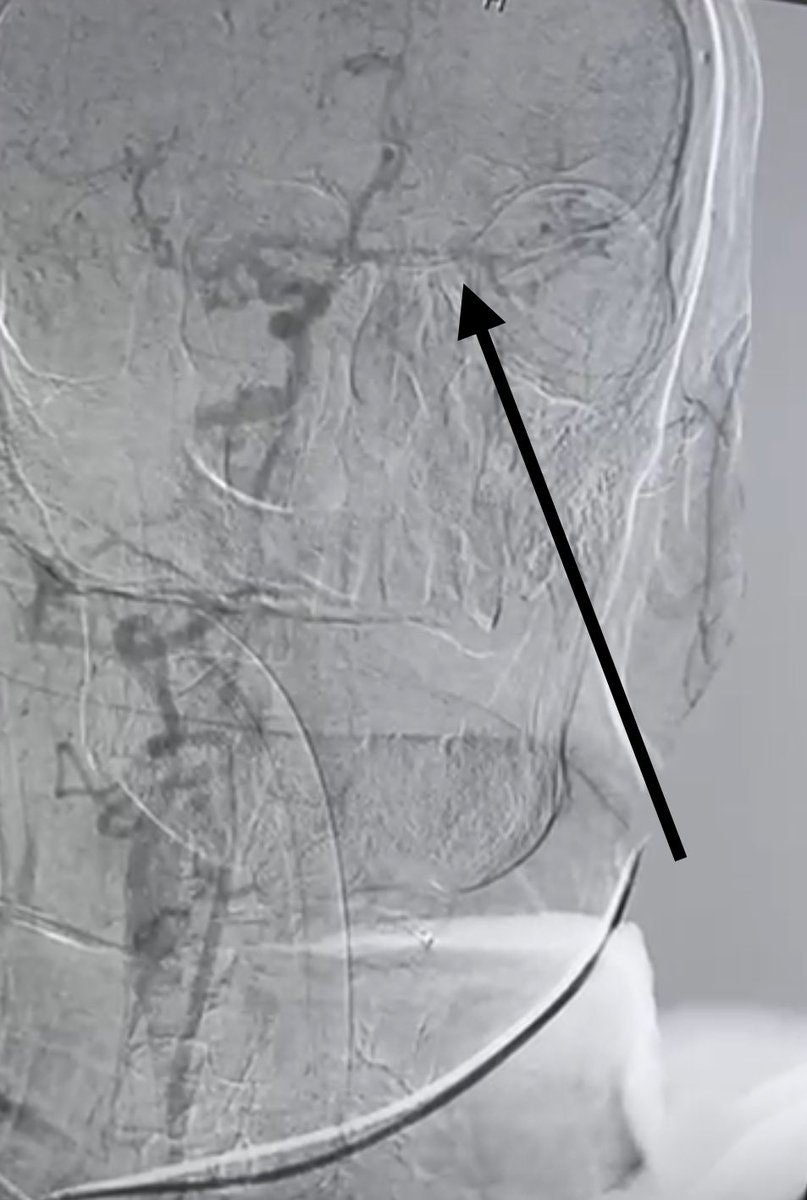

حالة من أصعب الحالات التي أجريتها لمسن ثمانيني يعاني من جلطة حادة أدت إلى شلل حاد في الجهة اليمنى من الجسم مع صعوبة في الإدراك والتحدث. القسطرة أكدت وجود تسلخ حاد في الشريان السباتي الأيسر وبحمد اللّٰه تم سحب الجلطات وإعادة التروية. بفضل اللّٰه المريض أصبح قادرًا على التحدث

حالة من أصعب الحالات التي أجريتها

لمسن ثمانيني يعاني من جلطة حادة أدت إلى شلل حاد في الجهة اليمنى من الجسم مع صعوبة في الإدراك والتحدث.

القسطرة أكدت وجود تسلخ حاد في الشريان السباتي الأيسر وبحمد اللّٰه تم سحب الجلطات وإعادة التروية.

بفضل اللّٰه المريض أصبح قادرًا على التحدث